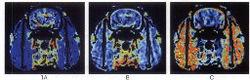

腎腫瘤組織的感興趣區域及其TDC曲線CT 灌注成像有 非去卷積法和 去卷積法,其原理是基於對比劑具有放射性同位素的彌散特點,通過從靜脈團注對比劑,在同一區域行重複快速 CT 掃描,建立動脈、組織、靜脈的時間密度曲線(TDC ),並通過不同的數學模型計算出灌注參數及彩色函式圖 ,從而對組織的灌注量及通透性作出評價。